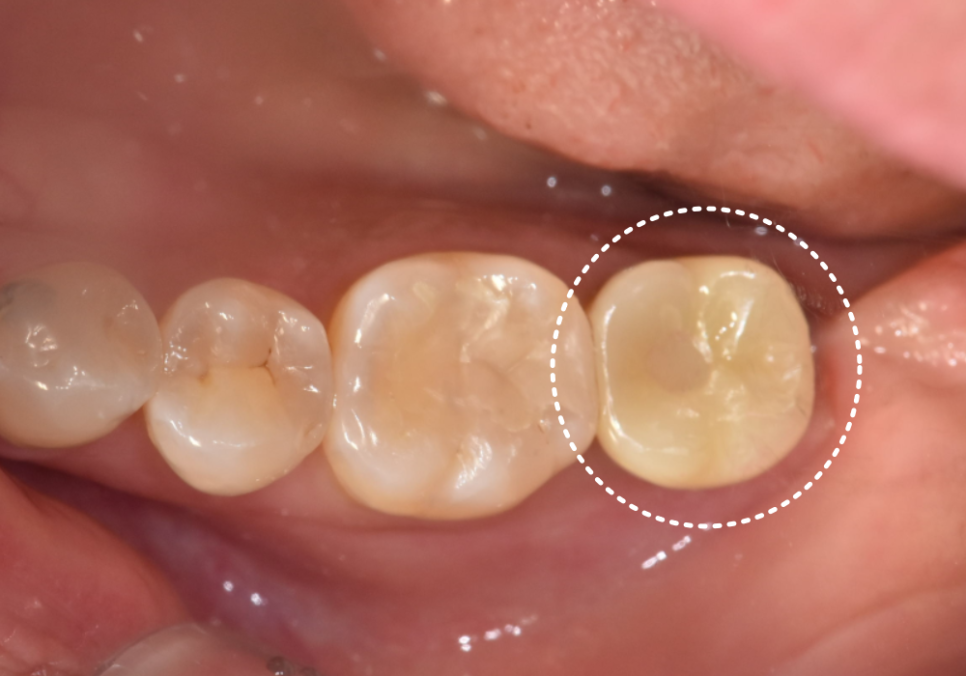

최근 한 여성 환자분께서 왼쪽 끝 어금니가

자꾸 욱신거린다며 저희 치과를 찾아주셨어요.

겉으로 보기에는 씌운 치아(크라운)가

아주 멀쩡해 보였고

환자분께서도 2년 전에

신경치료를 이미 받았던 치아라

왜 다시 아픈 건지 무척 의아해하셨는데요~